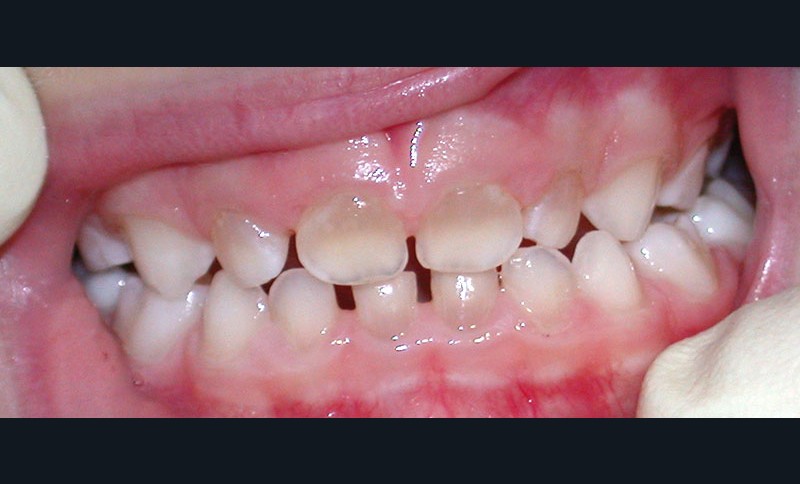

Teinte opalescente grise à jaune ambrée, couronnes globuleuses, calcifications intra-pulpaires, racines fines et courtes, attrition précoce, nécrose aseptique… Ces anomalies cliniques et radiographiques décrivent le tableau de la dentinogenèse imparfaite (DI) isolée de type 2. Cette anomalie génétique à transmission autosomique dominante est liée à un défaut de DSPP, gène de la sialophosphoprotéine dentinaire [1, 2]. Des anomalies dentinaires similaires résultent également de mutations de ce gène. Les avancées en recherche génétique tendent à réunir ces pathologies sous une même étiologie.

Un diagnostic précoce est primordial, car il existe aussi une forme associée à une anomalie osseuse, l’ostéogenèse imparfaite. Le chirurgien-dentiste est donc au premier plan pour dépister ces anomalies et limiter dès le plus jeune âge leurs conséquences infectieuses, fonctionnelles et esthétiques.